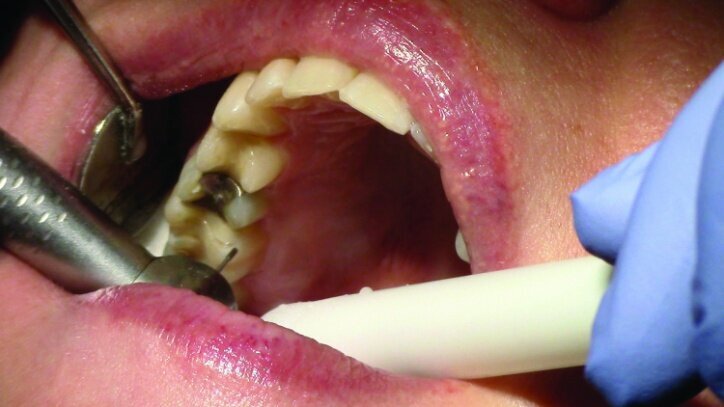

The remainder of the existing composite resin in #3 and the amalgam in #4 were removed. The occlusal surfaces of the preparations were blended into the interproximal areas using a KS2 bur to create smooth preparations (Figs. 10–15c). There was no retention or resistance form prepared to retain the restorations.

After gross occlusal reduction was completed, the remaining enamel ring was measured (Figs. 9a, b). The enamel rings were noted to be 1.5 mm, and the teeth were prepared for adhesively retained restorations. If the enamel rings were less than 1 mm, the teeth would have been prepared on the axial walls to create retention for cohesively retained crowns.